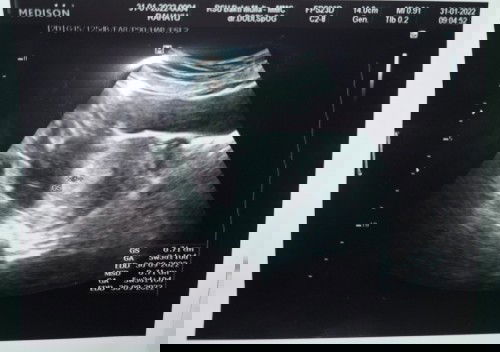

Usia kehamilan 8weeks Janin 6weeks

Hallo bun .. ada gak bun yang sama kayak aku.. usia kehamilan dihitung dari hpht sama usg beda 2minggu an.. agak worry sih..ini aku usg kemaren tanggal 14 februari usia janinnya 6w3d .. bener² beda 2minggu..di aplikasi dan hitungan bidan 8w3d.. tapi kemarin alhamdulillah janinnya sehat masyaAllah , dan udah bisa dengar detak jantungnya.. #bantusharing #hamilke2